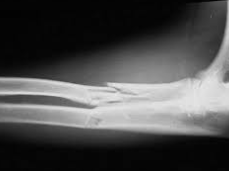

大動物橈骨と尺骨からなる前腕骨は、馬では生後約1年、牛では生後3~4年で互いに骨性に結合して不動になるため、成牛・成馬の前腕骨骨幹の骨折では、2骨が同時に損傷をうけることが多い。外力によるもののほか、馬では尺骨に疲労骨折がおこることがありま...